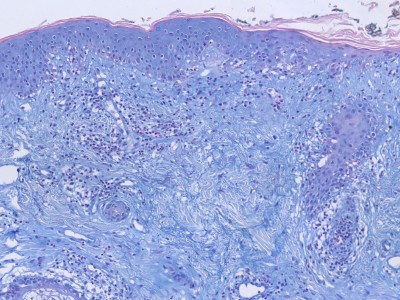

PA:

Grensvlakdermatitis met vacuolisatie van de basale membraan, en subepidermaal een perivasculair en periadnexaal lymfocytair infiltraat. De epidermis kan atrofisch zijn. Mucine depositie subepidermaal. De IF is meestal positief (lupus band).

Histologie lupus erythematosus Histologie lupus erythematosus

ingescande coupe (zoom) ingescande coupe (zoom)

Bron hoge resolutie PA-foto's: Kevin Kwee en Afdeling Pathologie MUMC. Klik op de afbeelding om in te zoomen.